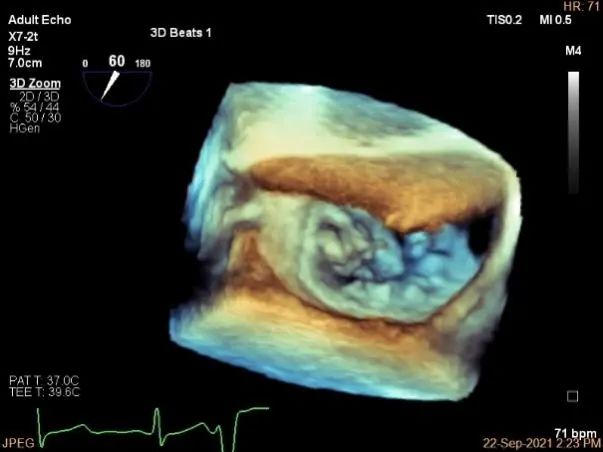

3D:P1区脱垂并腱索断裂,Width:11.4mm

3D-color:重度MR,4级